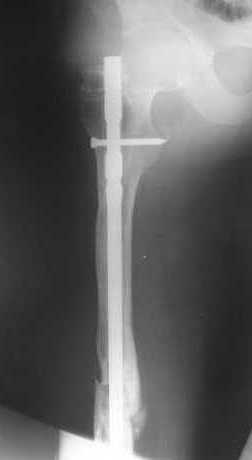

Пациенту М., 30-ти лет, 1,5 года назад в одной из московских больниц был выполнен остеосинтез бедренной кости штифтом UFN (диаметр штифта 9 мм).

К нам больной поступил с признаками ложного сустава бедренной кости, перелома

штифта и дистального блокирующего винта (images 1,2,3).